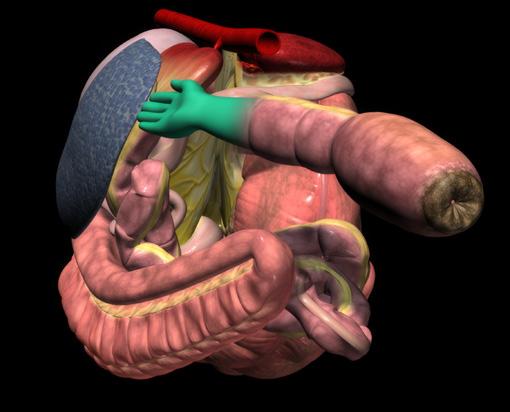

76 Reduce recurring entrapment colic

Jackie Bellamy-Zions talks to Dr. Nicola Cribb about new research showing how preventative surgery can reduce the risk of recurrent nephrosplenic entrapment colic in horses.

THE KING CHARLES III STAKES (5f ) | £700,000